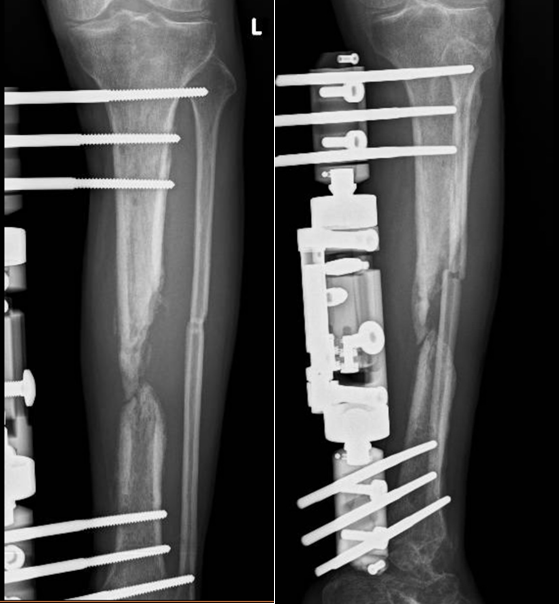

Gãy hở mất đoạn xương đã được cố định ngoài